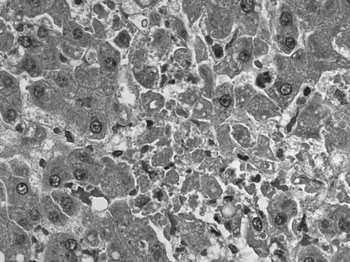

PMC3414043 12-0212-F2.png

Immunohistochemical staining of lymphocytic choriomeningitis virus antigens